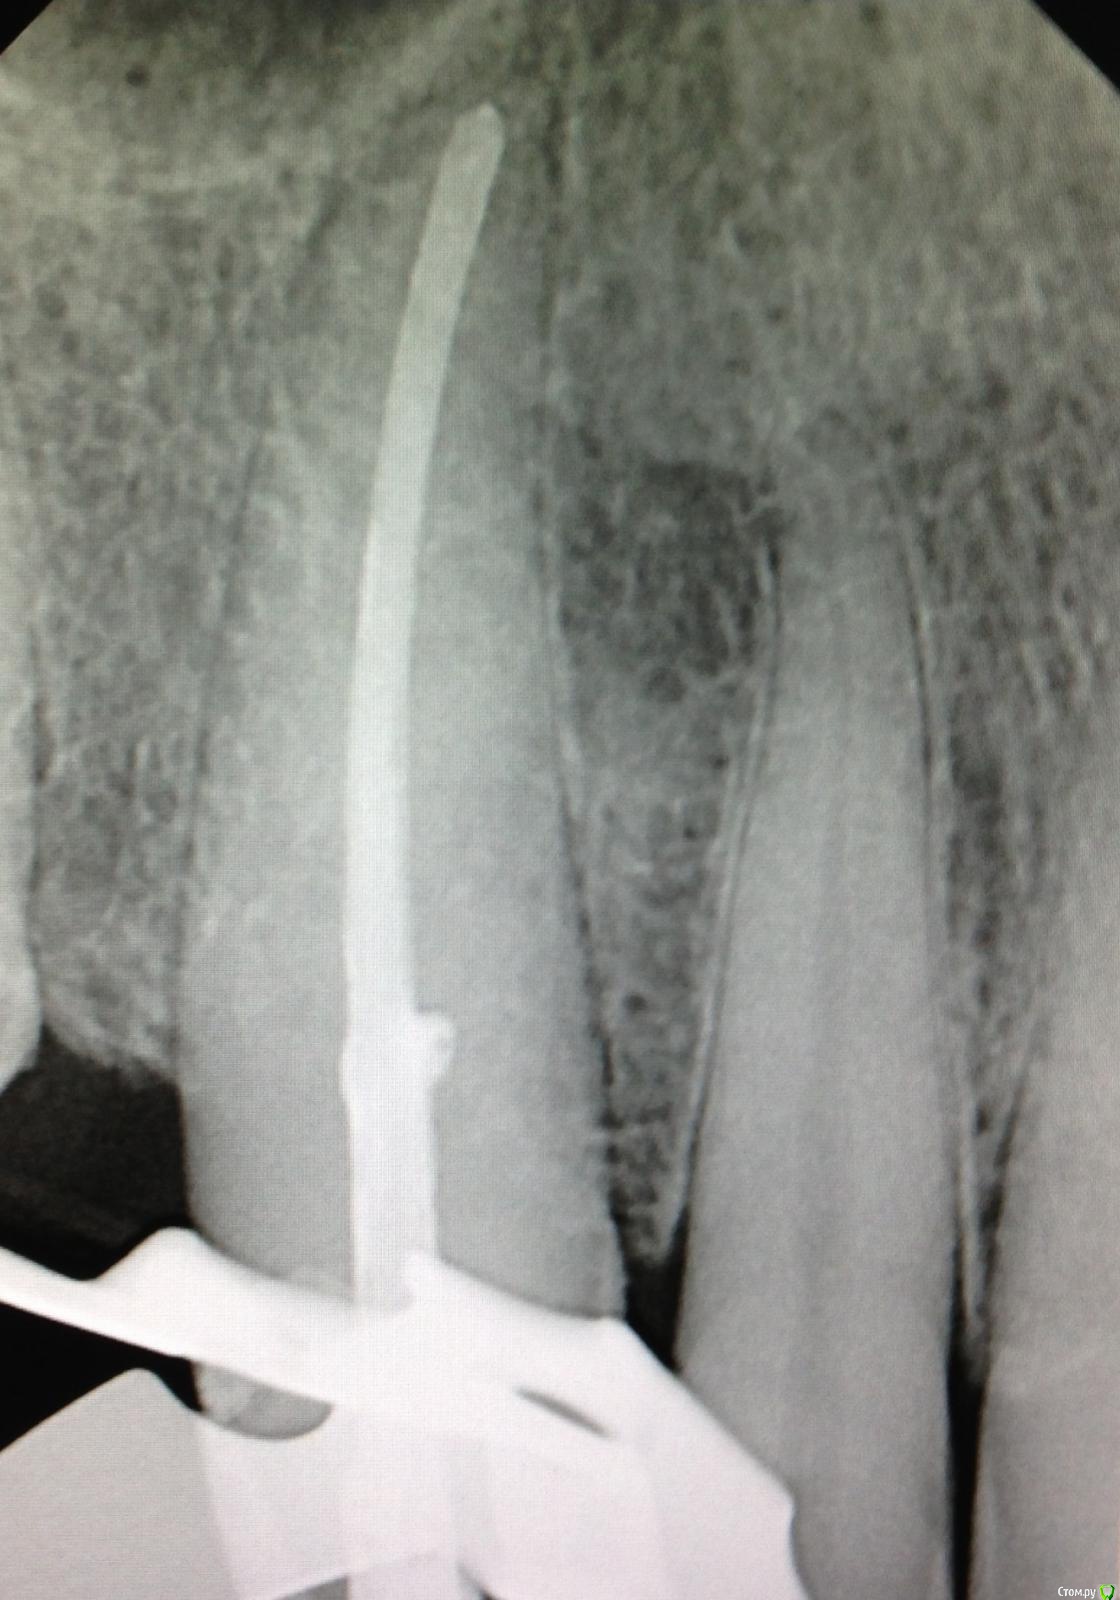

SSTi Опубликовано 12 декабря, 2014 Автор Поделиться Опубликовано 12 декабря, 2014 Еще 1 пульпитный красавчик Ссылка на комментарий